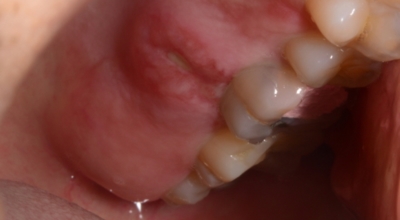

2. 구내염 원인 - 카타르성 구내염

카타르성 구내염 원인은 대부분 틀니 혹은 교정기에 접촉해서 상처가 나거나, 뺨의 안쪽을 이로 씹었을 때 나타나는 세균의 번식 과 같은 까닭으로 일어나게됩니다. 입의 점막이 붉게 붓거나 물집이 생기기도 해요. 아프터성 구내염과 달리 경계가 불명료하고 타액의 양이 올라가 구취가 발생하던가 입안이 뜨거워질 수 있죠. 그리고 미각이 둔해지는 경우도 있답니다.